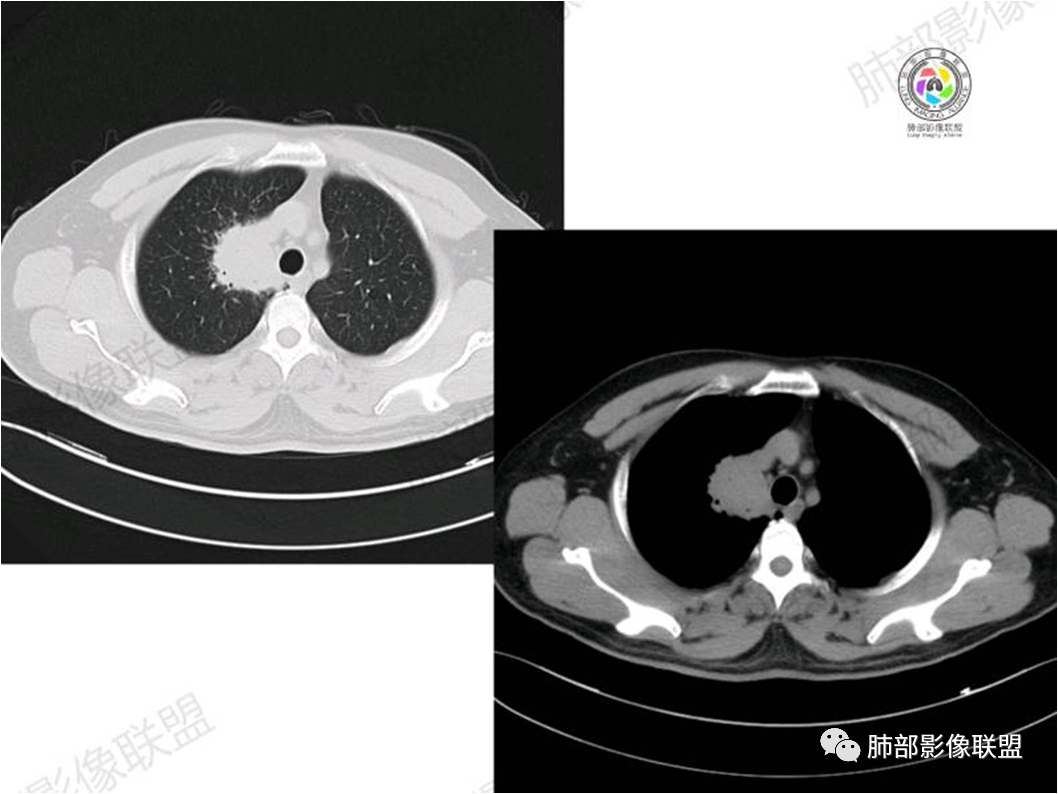

胸部CT:

病理结果:MALT

肺内黏膜相关淋巴组织淋巴瘤(MALT)

黏膜相关淋巴组织(Mucosa associated lymphoid tissue, MALT)淋巴瘤是来源于黏膜相关淋巴 组织边缘带的低度恶性非霍奇金B细胞淋巴瘤。肺MALT淋巴瘤较为罕见,约占淋巴瘤的0.14%~1%,易被误诊为肺炎或肺癌。

MALT淋巴瘤影像表现为实变、结节及磨玻璃影,其中实变是其特点,胸膜下或支气管血管束节段性分布具有特征性,跨叶征较常见,这可能与肿瘤细胞进入血循环后往往又回到上皮黏膜部位,它们从一处黏膜到另一处黏膜,但不会到外周淋巴组织等有关。国外多名学者的影像-病理研究报道认为其病理学基础是由于肿瘤细胞沿支气管血管束周围间质及胸膜浸润生长,形成小叶间隔增厚、支气管血管束增粗等间质性改变,进一步浸润肺泡壁、充填肺泡腔。

①实变的出现率100%,多表现为两(89%)或单肺多发,密度均匀,与邻近胸壁肌肉的密度大致相等,少见钙化(15%),这与病灶内血管保持 完整,血供丰富,且肿瘤生长缓慢,对缺氧耐受好,不易坏死有关。边缘磨玻璃影或晕征具有特异性,其病理学基础是肿瘤细胞对小叶间隔、肺泡壁的淋巴瘤样浸润;

③扩张的充气支气管为其较特征性的表现,出现率约为89%,支气管管壁无破坏,支气管常扩张并达病灶的边缘,这与炎症性肺癌明显不同,其病理学基础是肿瘤起源于肺间质,肿瘤细胞沿着脏器解剖结构生长,周围增生的结缔组织牵拉导致支气管扩张,因而这类支气管扩张在肿瘤治疗后有时可消失;

④血管造影征是另一 点,强化的肺血管形态及走行正常,无扭曲或增 粗,其病理学基础为肿瘤细胞沿间质增生浸润,不破坏血管或支气管,病灶内肺支架结构完整,本研究发现率为75%;